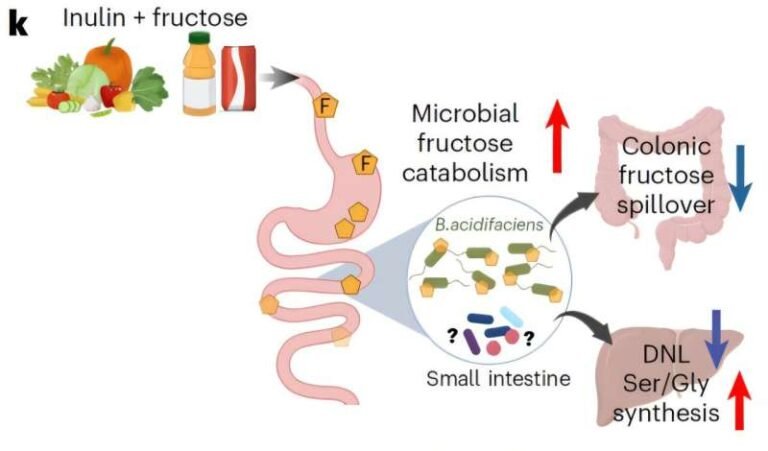

NutriciónRiesgo desigualInseguridad alimentaria y dietas poco saludables elevan vulnerabilidad poblacional.

InvestigaciónVacunas e IAEnsayos, vigilancia genómica y salud digital avanzan como herramientas estratégicas.